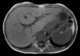

Esophageal leiomyomatosis

A leiomyoma, also known as fibroids, is a benign smooth muscle tumor that very rarely becomes cancer (0.1%). They can occur in any organ, but the most common forms occur in the uterus, small bowel, and the esophagus. [Source: Wikipedia ]